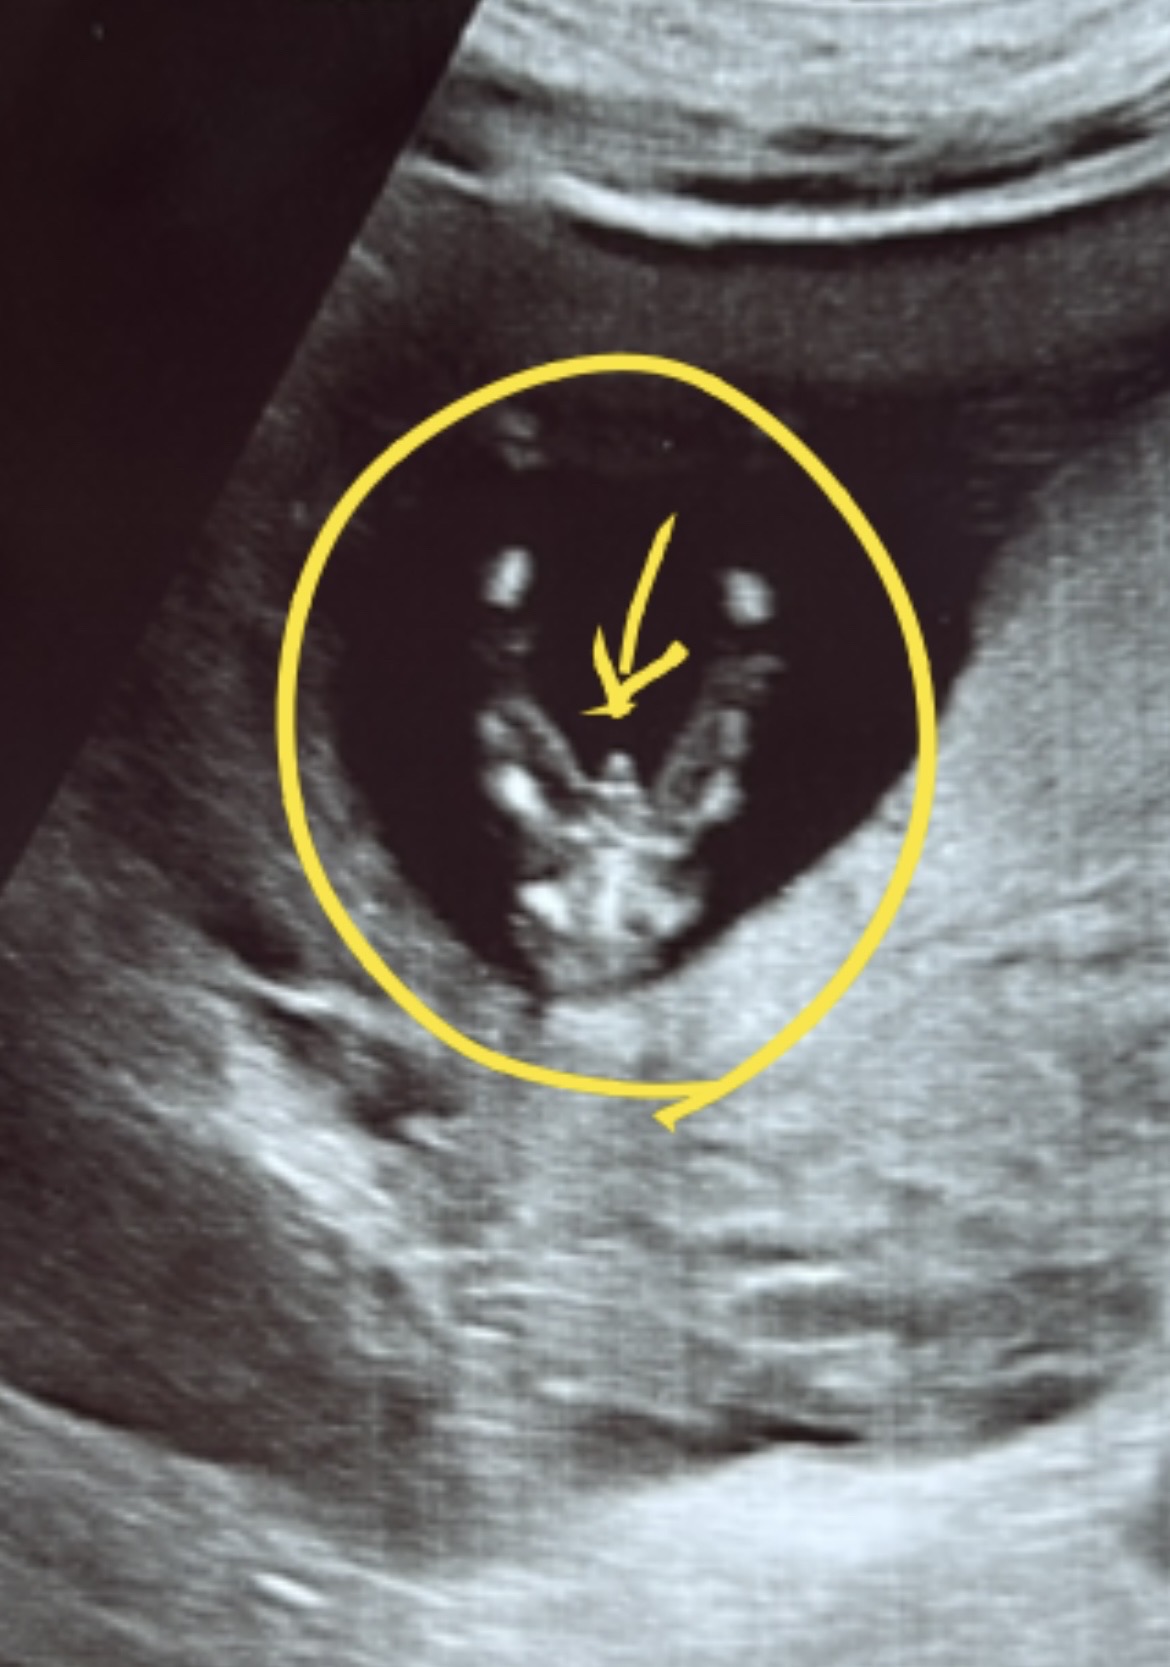

12주 4일, 성별 강제 공개 당함ㅠㅎ

숨길 수 없는 존재감🌶️ 심장 소리, 난황 위치, 땡기는 음식 다 의미 없던걸로…ㅎㅎ 딸이길 염원한 남편 억장와르르ㅋㅋㅋ

의사쌤도 이 시기엔 조금 튀어나와 보인다고는 하셨는데ㅎㅎ 근데 유독 튀어나와 보이긴 하죠? 아들 같아요! 하시더라구용ㅎㅎ